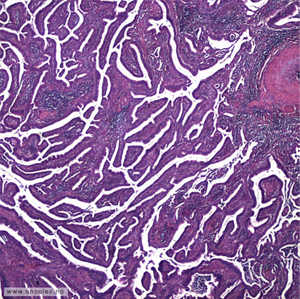

Livmorhalskreft starter vanligvis i plateepitel eller sylinderepitel, altså slimhinnens overflatelag.

Karsinomer (kreftsvulster) starter ofte med forstadier, såkalt intraepiteliale neoplasier (CIN) grad 1,2 eller 3.

Plateepitelkarsinom utgjør cirka 85%, adenokarsinomer cirka 10% og øvrige typer cirka 5 % av all kreft i livmorhals.

Bildeeksempler